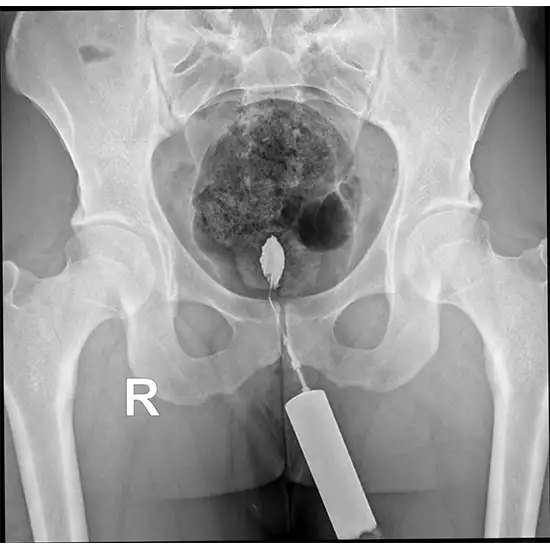

X-Ray Fistulography

Fistulography is an x-ray examination technique used to look inside a fistula. An X-ray is obtained after the fistula has been prepared after administering contrast material through the fistula's exterior entrance in a sterile environment. We make use of a contrast medium called Vistavu, which is a non-ionic x-ray contrast medium.

The length, shape, and direction of a fistula, as well as its relationship to a hollow organ (such as the stomach, intestine, or bile duct), as well as to a foreign body or a focus of inflammation, can be determined with the help of a technique called fistulography. This enables the treating physician to select the most effective treatment for the patient.